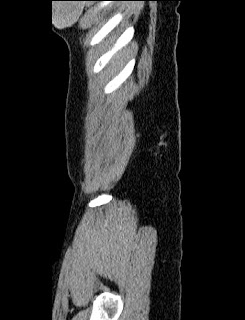

44 year old female with a long medical history. Undergone repeated surgeries for prox. 30 years. Not always fully understood what the purpose has been or expected outcome from all the procedures.

2010